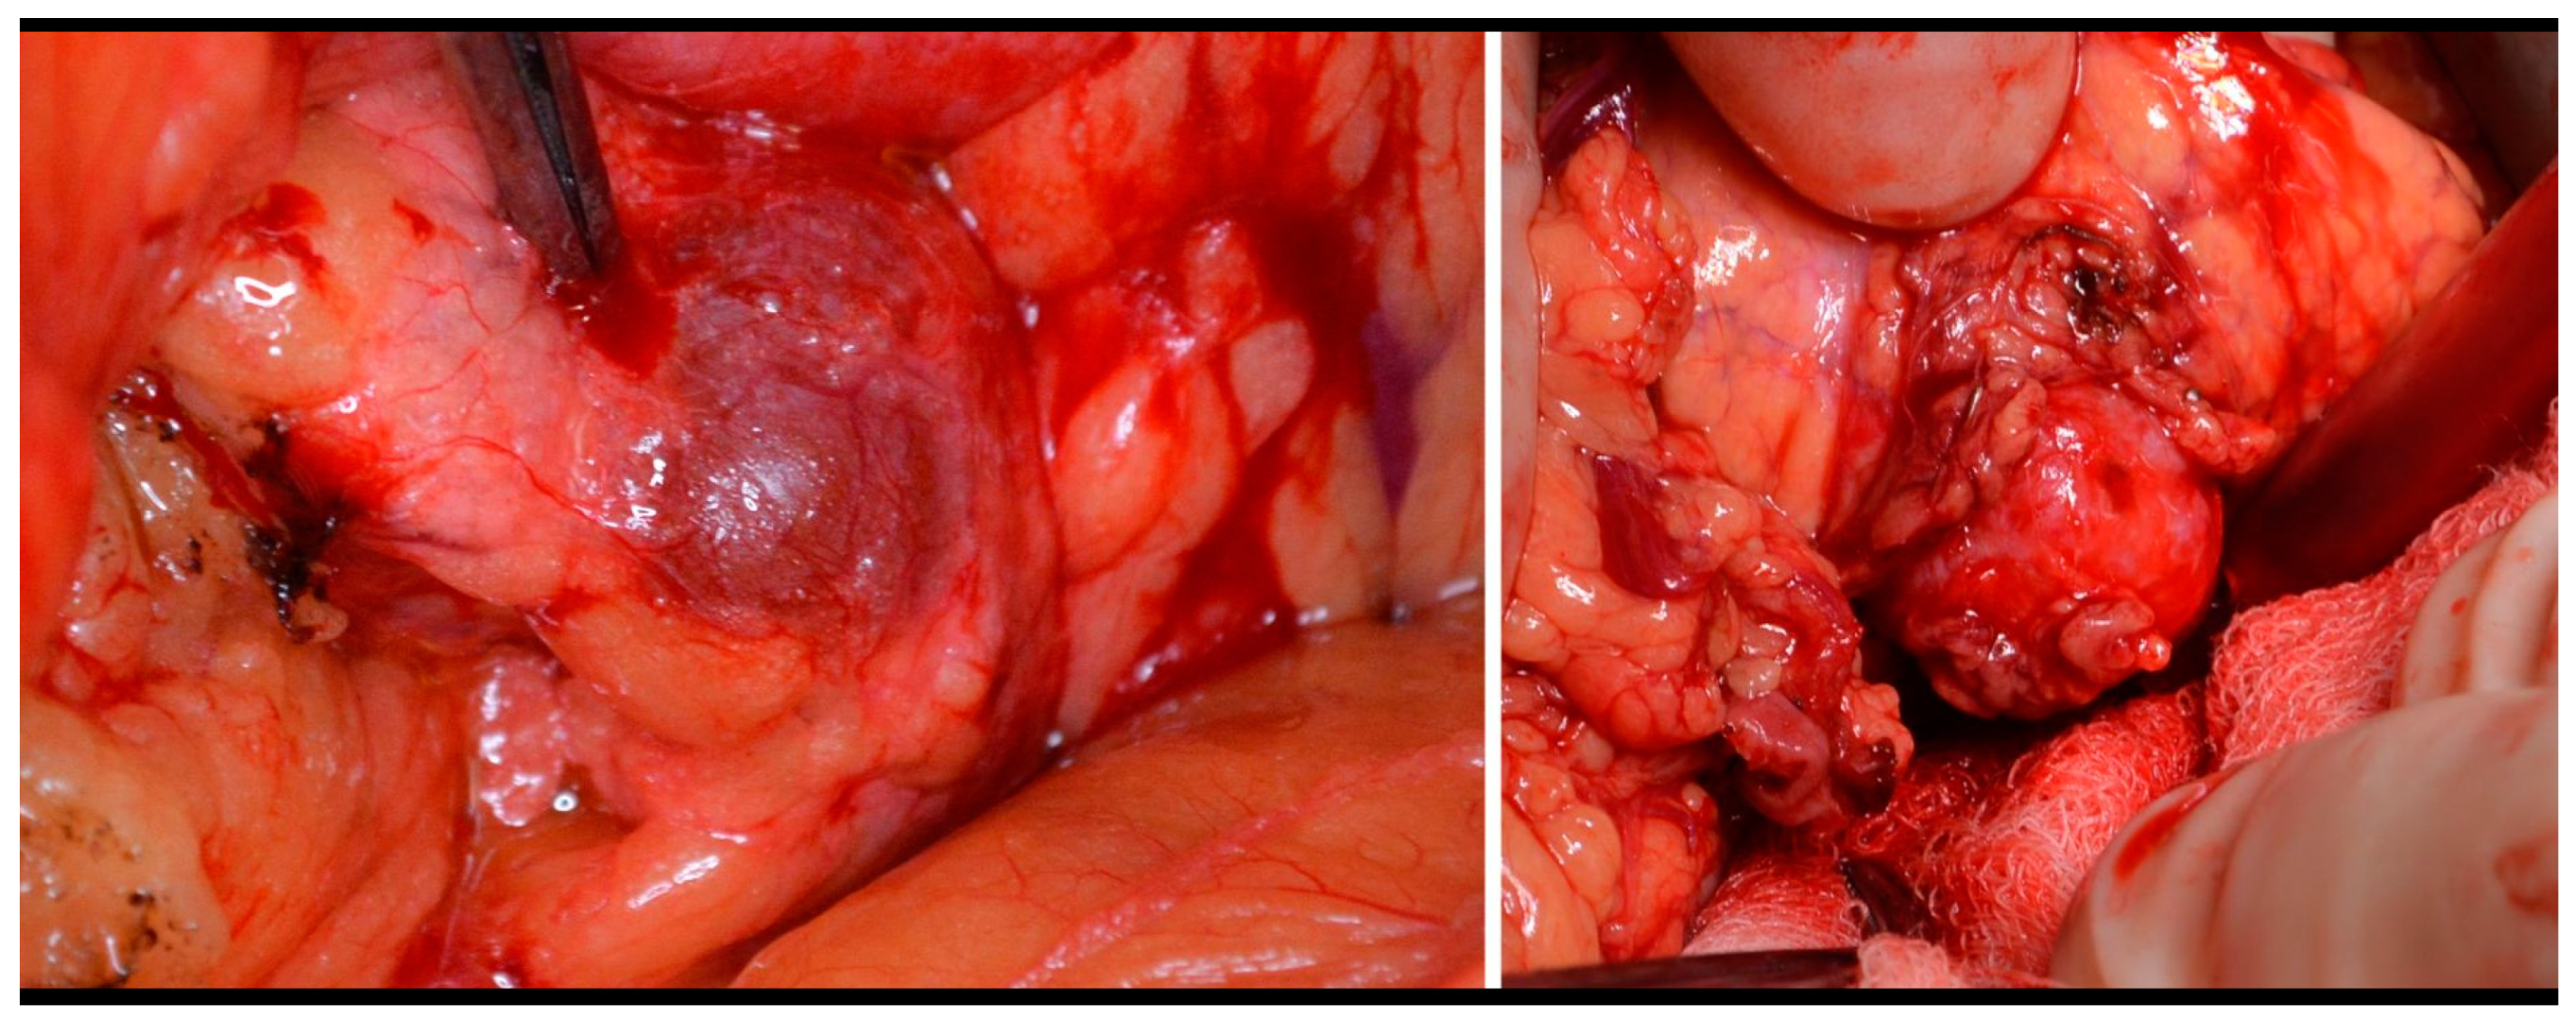

The type of surgery performed depends on the tumor localization, its size, and its relationship to the main pancreatic duct and surrounding vessels and organs. Enucleation was performed on 50% of the patients. (Figure 3). In some cases, we added Roux-Y pancreaticojejunoanastomosis. The second most frequently used procedure was left-side pancreatectomy (37%), with or without splenectomy. Other types of surgery were indicated less frequently (Table 3). The laparoscopic approach was used on 33 patients, but conversion was necessary in 2/3 of these cases. The main indication for conversion was uncertainty about the localization of the tumor. Five patients underwent surgery twice, and one female was underwent surgery four times (three of these patients are mentioned above.

Figure 3. Insulinoma—perioperative view and enucleation.